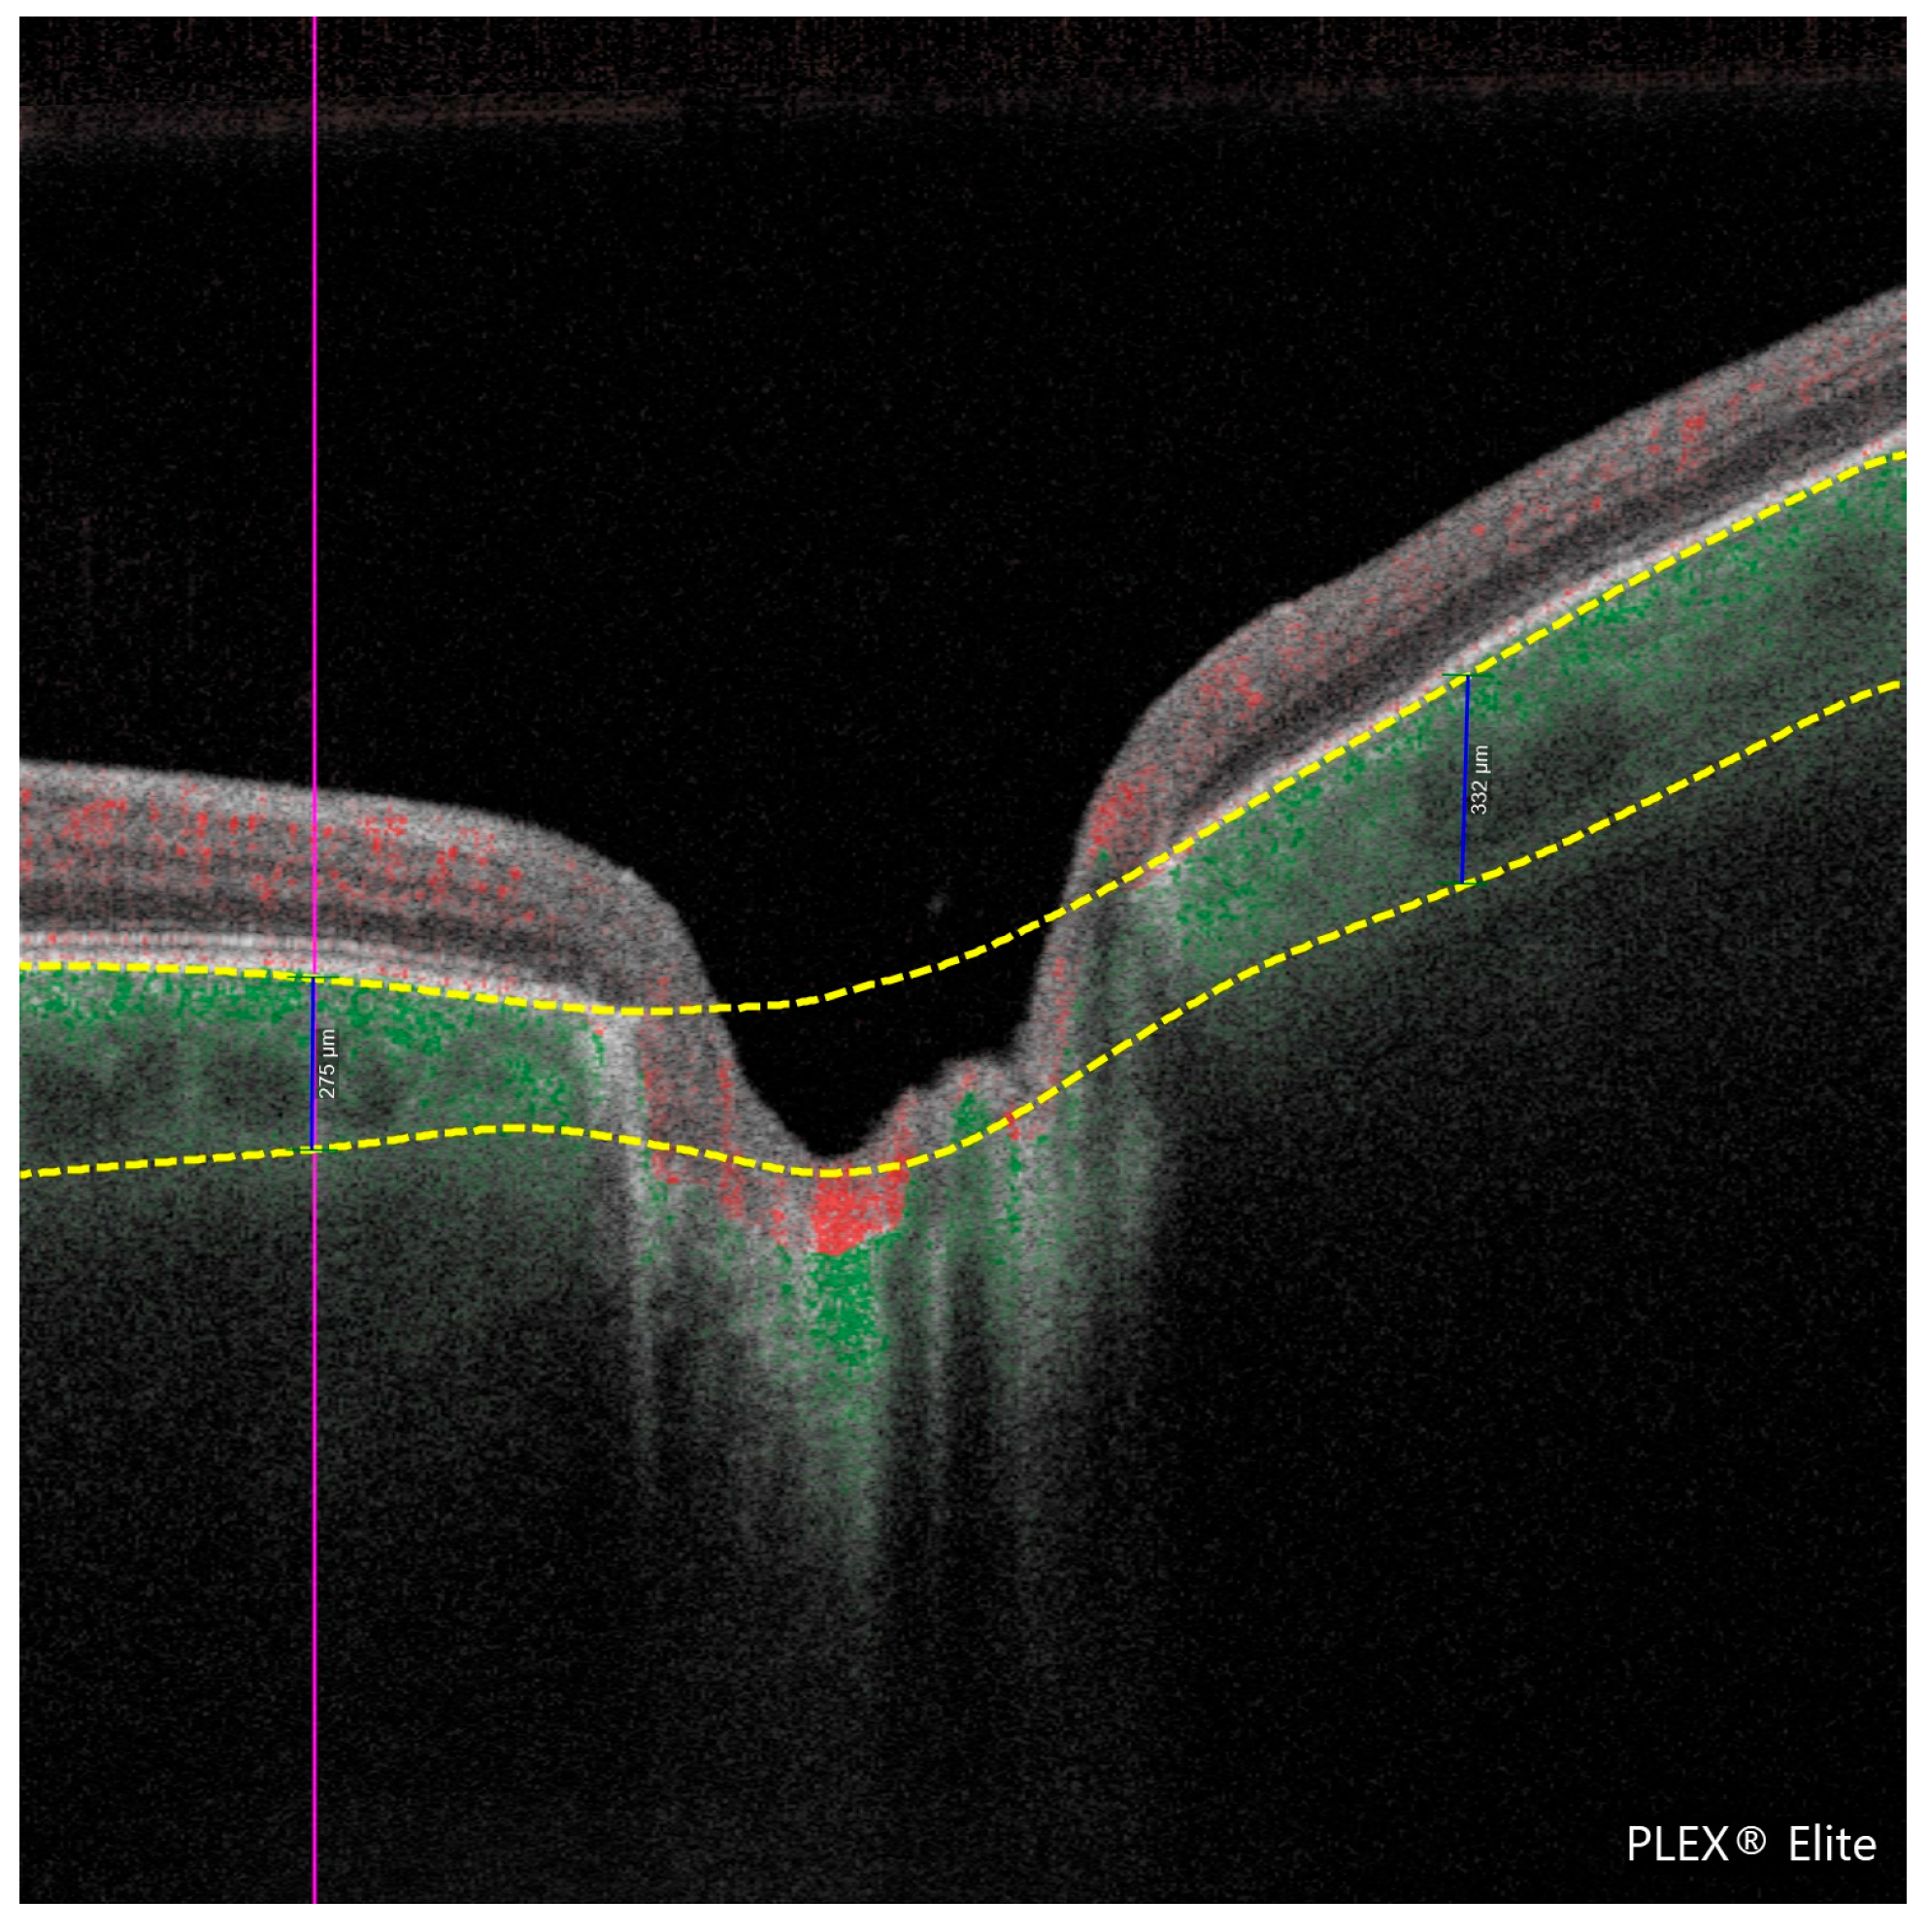

PCT is the thickness of the choroid (the vascular layer beneath the retina) measured in the peripapillary region. In this study, PCT was manually measured at a fixed distance of 1000 μm from the optic disc margin in the four peripapillary quadrants (temporal, nasal, superior, and inferior) using high-resolution en face OCTA images. Measurement points were selected based on two anatomical landmarks, specifically from the outer border of the retinal pigment epithelium (RPE) to the inner scleral boundary. This standardized approach was applied consistently across all subjects to ensure reproducibility and minimize measurement bias. The methodology is illustrated in Figure 1 and Figure 2.

Figure 2. Cross-sectional optical coherence tomography (OCT) image of the retina acquired using the PLEX® Elite 9000 system. The image illustrates the peripapillary choroidal thickness (PCT) measurements in two quadrants, with vertical blue lines indicating thickness values of 275 μm (left) and 332 μm (right). Red and yellow dashed lines delineate anatomical boundaries used for manual measurement, extending from the outer border of the retinal pigment epithelium to the inner scleral surface, at a fixed distance of 1000 μm from the optic disc margin.